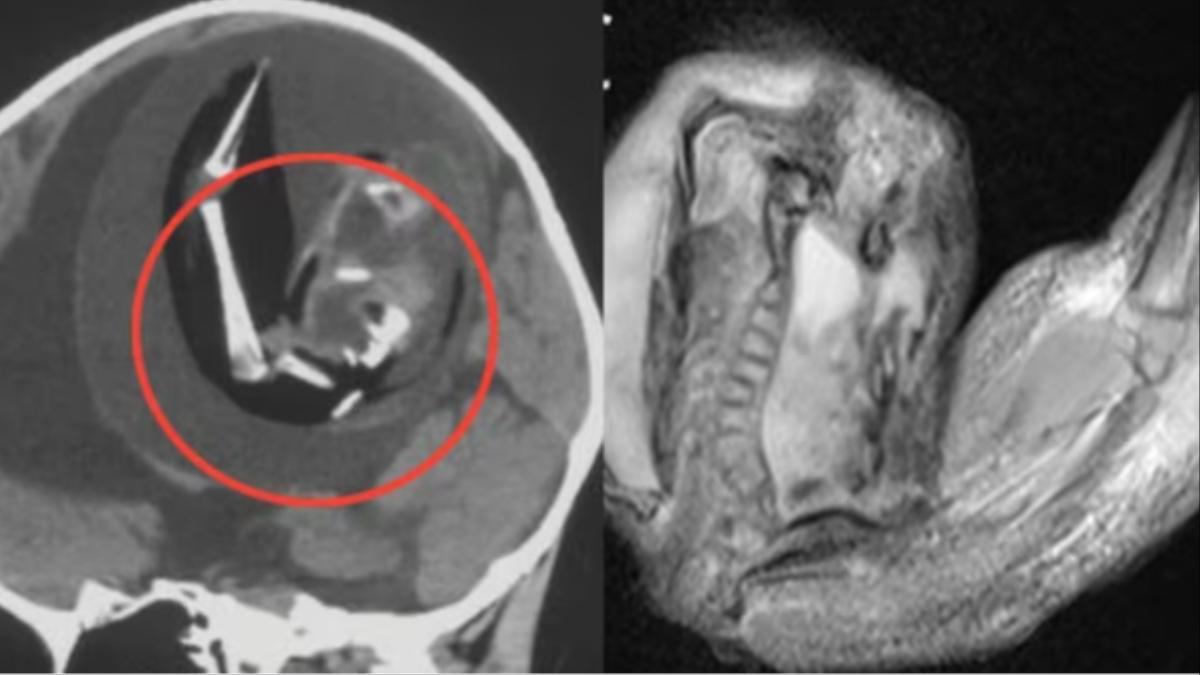

बच्ची के दिमाग में पाया गया अजन्मा भ्रूण

बता दें कि इस बच्ची का जन्म एक साल पहले हुआ था जन्म के बाद से ही बच्ची के सिर का साइज लगातार बढ़ने लगा था. ऐसे में बच्ची के माता-पिता उसे अस्पताल ले गए जहां उसका सिटी स्कैन किया गया. जांच करने के बाद डॉक्टर्स ने पाया कि बच्ची के दिमाग के अंदर एक भ्रूण मौजूद था. डॉक्टर्स ने बताया कि बच्ची के दिमाग में यह अजन्मा भ्रूण 4 इंच तक बढ़ चुका था और इसकी कमर, हड्डियां और उंगलियों के नाखूनों का भी विकास हो रहा था. डॉक्टर्स ने बताया कि इस अजन्मे भ्रूण का विकास बच्ची के दिमाग के अंदर उस वक्त से हो रहा था, जब बच्ची अपनी मां की कोख में थी.

बच्ची के दिमाग से निकाले गए इस भ्रूण की जीनोम सीक्वेंसिंग में खुलासा हुआ कि यह भ्रूण इस बच्ची का ही जुड़वां था. मेडिकल साइंस में इस स्थिति को फीटस इन फीटू कहा जाता है.  इस स्थिति में मां की कोख में पल रहे दो भ्रूण में से एक भ्रूण का विकास दूसरे भ्रूण के अंदर ही होने लगता है. ऐसा तब होता है जब दोनों भ्रूण सही तरह से अलग नहीं हो पाते हैं.